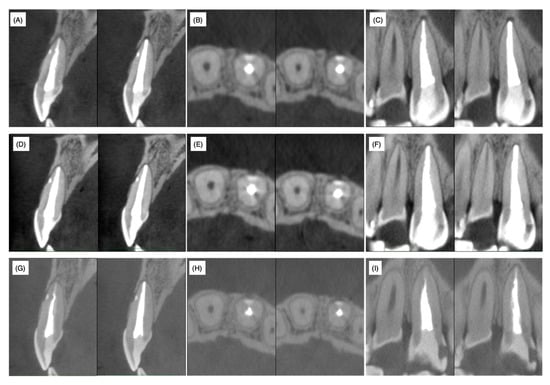

Fourteen days after root canal obturation, the accessible palatal cavity was filled with the composite resin for a permanent restoration. Three months, one year and two years after root canal obturation, CBCT analyses were performed. The lateral canal remained closed by the filled resin material even after two years and the absence of labial bone resorption was chronologically confirmed on cross, sagittal and horizontal sections (Figure 5). Furthermore, no recurrence of gingival swelling was confirmed on photographs and no clinical symptoms were observed.

Non-surgical treatment was conducted to mechanically and chemically disinfect the main root canal. However, the clinical symptoms and signs did not improve necessitating the need for surgical treatment. A slight exudate infiltrated the paper point only when it reached the orifice of the lateral accessory canal through the main root canal. Therefore, the root canal infection was mainly due to communication with the periodontal area surrounding the foramen of the laterally localized accessory root canal and infection of the accessory root canal and the surrounding dentin. It is widely accepted that surgical treatment should be conducted only when non-surgical endodontic treatment has failed. In the present case, our decision for surgical treatment might be considered to have been early. We were unable to wait for a tissue healing response under non-surgical treatment due to the limited period of hospital attendance. MTA, composite resin, glass polyalkenoate cement and o-ethoxybenzoic acid cement (EBA cement) are the alternative choices for filling materials of perforation spots. Among these materials, MTA is widely accepted as the best from a periodontal tissue regeneration point of view. However, MTA requires 3−4 mm of thickness to block microleakage [9,10]. In the present case, the horizontal accessory canal had a length of 2 mm at the labial side of the root in the sagittal section (Figure 3); therefore, in order to prevent detachment of the filling material during subsequent supportive mechanical and chemical endodontic treatments, the self-etching dentin-adhesive system and composite resin were selected based on their strong adhesive strength and chemical stability. The composite resin (Beautifil Flow F02®, Shofu) used in this case contains an S-PRG filler and is categorized as a giomer [25]. When the coronally positioned flap operation was conducted to restore gingival recession, the gingival epithelium was re-attached to the GIOMER surface to construct a long junctional epithelium and the root coverage rate of the GIOMER surface was higher than that of glass ionomer cement and GIOMER-free composite resin surfaces [26]. Thus, the relatively higher biocompatibility of the GIOMER may have reduced the radiolucent area and regenerated alveolar bone tissue even in the area hanging over the resin at one and two years after the surgery (Figure 5D–I). MTA has been applied to seal perforations in roots and the bottom of the pulp chamber with a good prognosis, without inducing periodontal tissue inflammation in clinical settings and in in vivo experimental animal models [27,28]. According to a meta-analysis of the treatment outcome of repaired root perforations [29], an overall success rate of 72.5% was estimated for non-surgical repair of root perforations and the rate increased to 80.9% only when MTA application cases were included. In a long-term evaluation of the repair of root perforations with MTA application [30], which was one of the clinical analyses used in the reported meta-analysis [29], teeth were classified into a ‘healing’ group if only two or less of the five clinical and radiographic findings, namely, radiolucency adjacent to the perforation site, continuing root resorption, clinical signs, clinical symptoms and loss of function, were identified at the time of evaluation. If we apply this rule in the present case, radiolucency was adjacent to the perforation site, clinical signs (the presence of sinus tract) and clinical symptoms (discomfort and pressure pain) were identified and only radiolucency adjacent to the perforation site was identified at pre- and postoperative stages (both post one and two years). These scoring results implied that the lesion was healed. Therefore, by considering the reduced radiolucent area at post one and two years, the resin containing S-PRG filler used in the present case can be regarded to possess an apparent regenerative ability equivalent to MTA cements. The possibility of minor leakage between dentin and MTA cement or MTA dropout due to mechanical and chemical stress was not excluded before treatment. Therefore, in addition to the application of MTA only being authorized for pulp capping treatment (not for perforation repair) under the Japanese health insurance system, we selected resin containing S-PRG filler as the filling material in this case.

Figure 5. Cone-beam computed tomography images at three months (A) sagittal, (B) horizontal and (C) coronal; one year (D) sagittal, (E) horizontal and (F) coronal and two years (G) sagittal, (H) horizontal and (I) coronal after root filling.